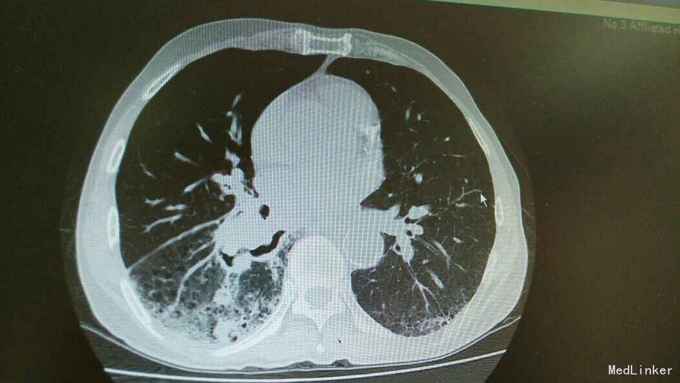

主诉:活动后气促,胸闷1年,消瘦8月余。 病史:患者1年前无明显诱因出现活动后气促,胸闷,主要为胸骨段,爬坡可诱发,伴有咳嗽,白色粘痰。伴有体重下降。

查体:慢性病容,桶状胸,双肺呼吸音粗,右下肺可闻及少量细湿罗音。 辅查:胸部CT:考虑右下肺中央型肺癌并癌性空洞形成,右下肺阻塞性肺炎 ,右下肺动静脉受累,纵隔,双侧肺门多发淋巴结肿大。

诊断:中央型肺癌并阻塞性肺炎。 治疗:入院予以抗感染,止咳化痰等治疗。